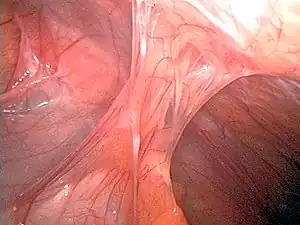

| Adhesions formed following appendectomy |